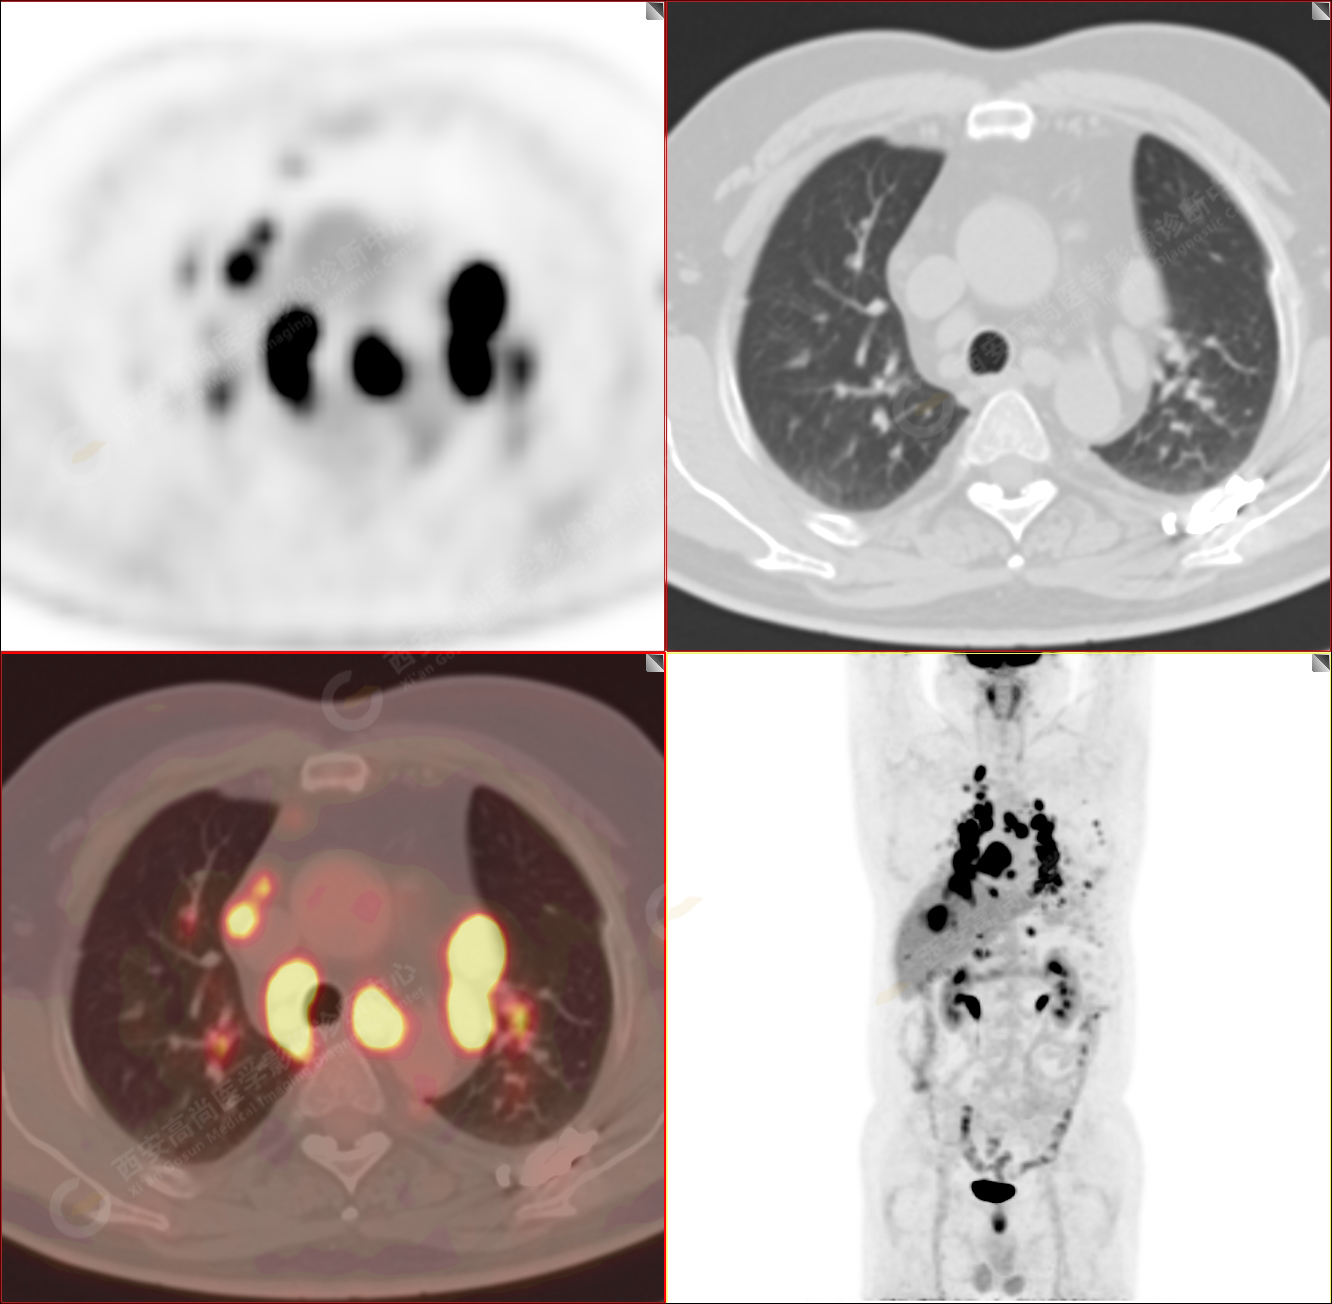

男性,53歲,頭暈半月入院,CT發(fā)現(xiàn)肺內(nèi)腫塊,雙肺多發(fā)大小不等實(shí)性及粟粒樣結(jié)節(jié),雙肺門(mén)及縱隔多發(fā)腫大淋巴結(jié)。病程中無(wú)發(fā)熱、胸悶氣及胸部不適。既往:左側(cè)肋骨外傷史。

PET-MR圖像